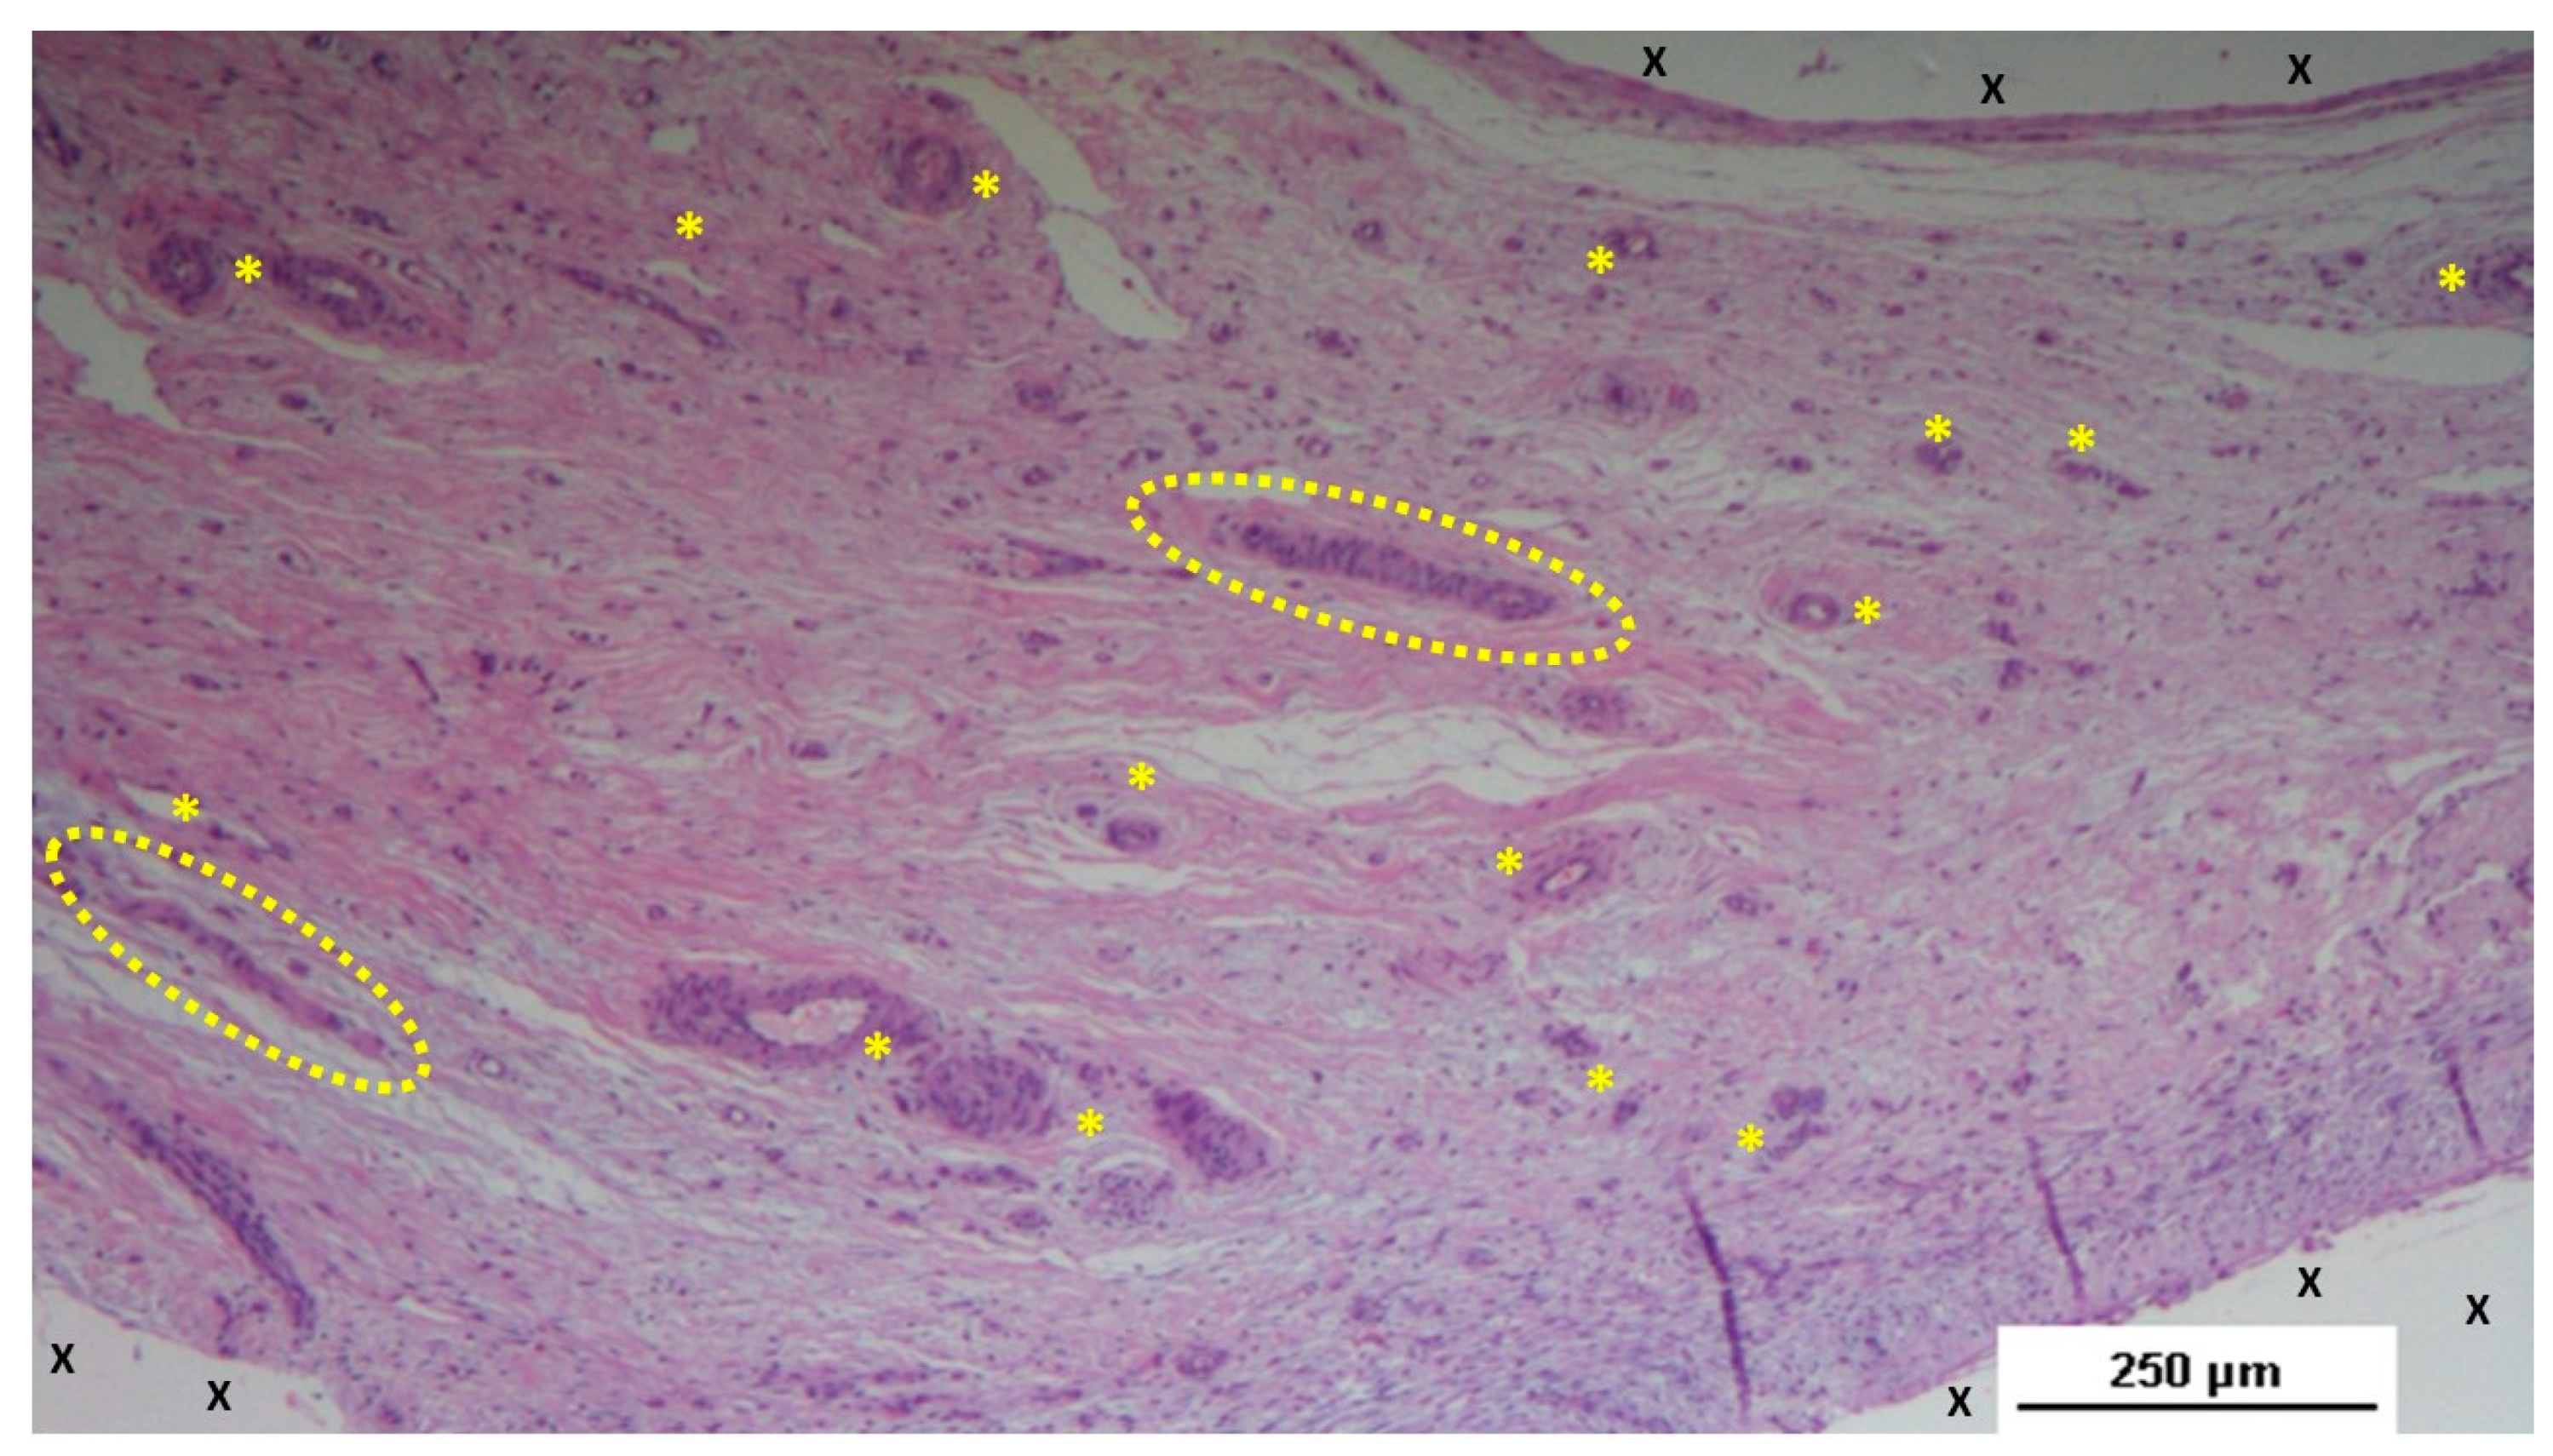

Two pathologists evaluated the tissue samples and the related histological sections in blinded manner regarding the postoperative period. Tissue samples taken from the scaffold of the S&S device during the short-term period (3-5 weeks post-implantation) revealed an abundant presence of early-stage vascular clusters near the scaffold material, with minimal inflammatory response observed (Figure 3, Figure 4, Figure 5 & Figure 6).

Figure 3. Biopsy from the 3D scaffold of the S&S device, excised four weeks post-implantation (short-term). Microphotograph reveals numerous newly formed vascular structures in early development (*) adjacent to the S&S device fabric (X) with negligible inflammatory response in well-perfused connective tissue. The inset (right upper corner) provides a magnified view of these developing vascular elements. HE 50X (main image) and HE 100X (inset).

Figure 4. Biopsy taken five weeks post-implantation from the 3D scaffold of the S&S device. Near the TPE fabric (X), no inflammatory reaction is present, but numerous vascular structures (*)—primarily immature veins—are visible. A yellow circle highlights a cluster of arterial elements in the early-stage of development. The inset (right upper corner) offers a detailed view of the arterial structures with developing muscular layers. HE 25X (main image) and HE 100X (inset).

Figure 5. Biopsy sample from the 3D scaffold of the S&S device, excised four weeks post-implantation. Close to the device fabric (X), a large arterial structure (yellow circle) is seen in its early developmental stage. No inflammatory elements are detectable near the device. HE 25X.